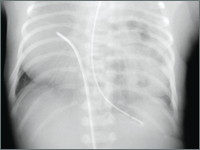

Grzyb A., Pruszyńska I., Stańczyk B.

Congenital diaphragmatic hernia (CDH) is a rare birth defect with a high mortality rate, resulting from pulmonary hypoplasia and pulmonary hypertension. In order to optimize treatment outcomes prenatal diagnosis is important, providing the opportunity to choose further management.